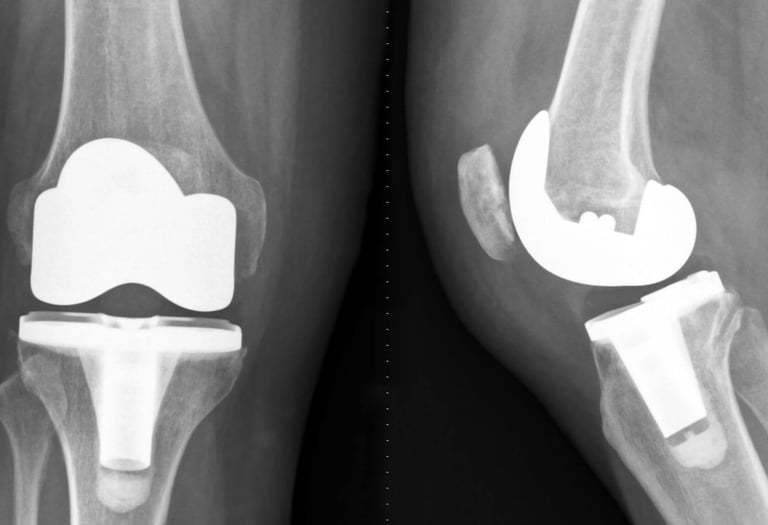

Advanced joint reconstruction using durable hip and knee replacement technology.

Reconstruction